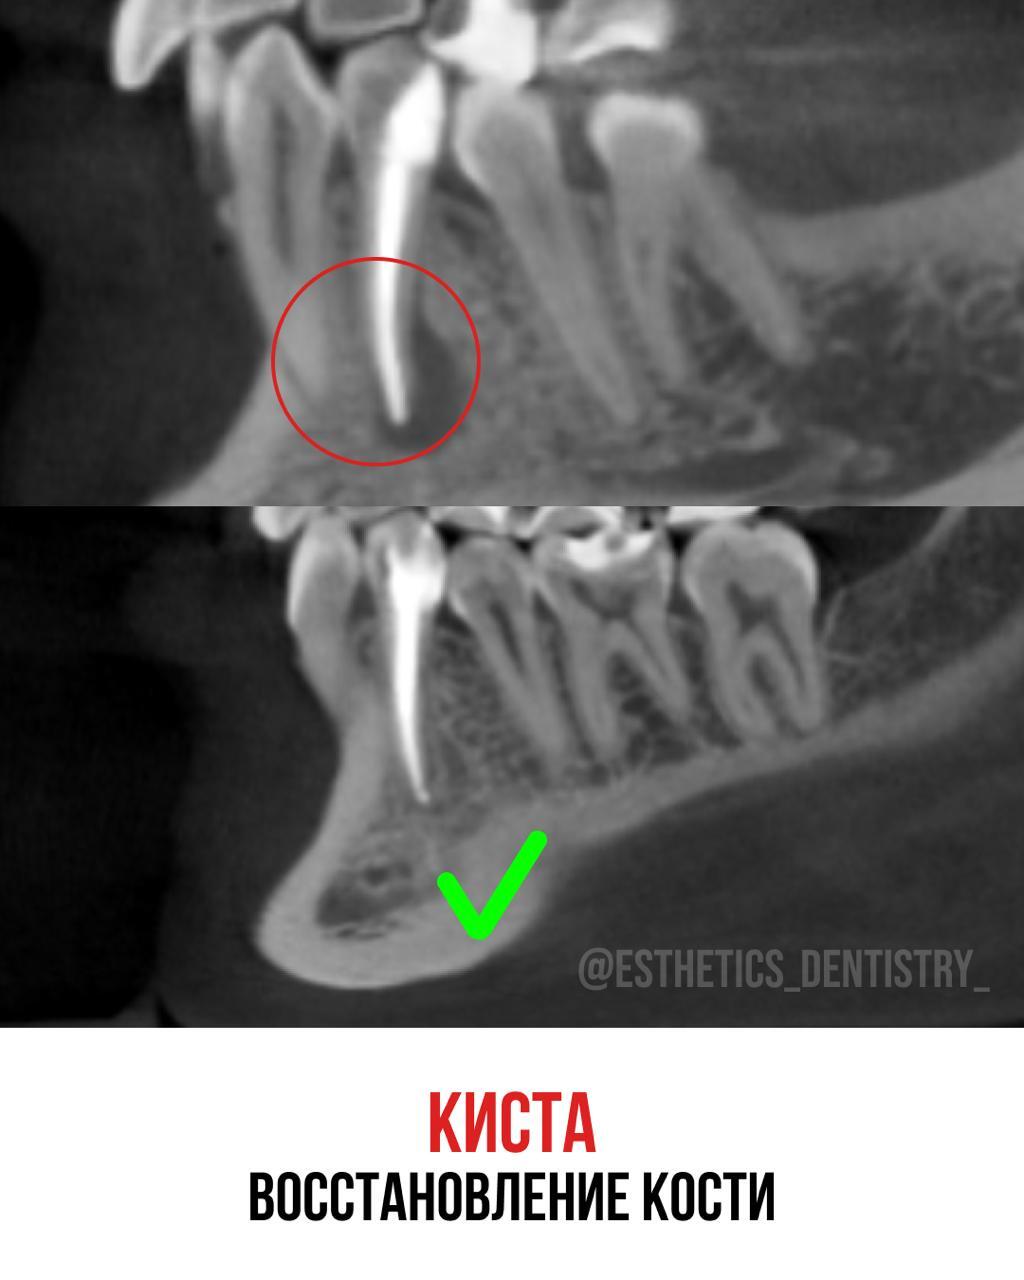

Кейс лечение кисты

Терапия